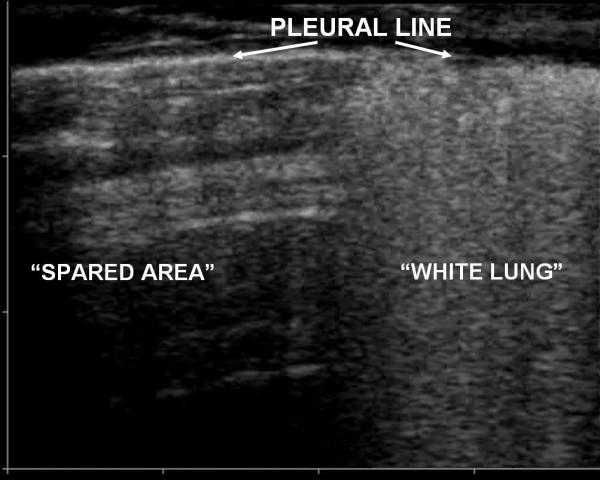

Ultrasound examination was focalised on finding in the two groups the presence of: 1) alveolar-interstitial syndrome (AIS) 2) pleural lines abnormalities 3) absence or reduction of "gliding" sign 4) "spared areas" 5) consolidations 6) pleural effusion 7) "lung pulse".AIS was found in 100% of patients with ALI/ARDS and in 100% of patients with APE (p = ns). Pleural line abnormalities were observed in 100% of patients with ALI/ARDS and in 25% of patients with APE (p < 0.0001). Absence or reduction of the 'gliding sign' was observed in 100% of patients with ALI/ARDS and in 0% of patients with APE. 'Spared areas' were observed in 100% of patients with ALI/ARDS and in 0% of patients with APE (p < 0.0001). Consolidations were present in 83.3% of patients with ALI/ARDS in 0% of patients with APE (p < 0.0001). A pleural effusion was present in 66.6% of patients with ALI/ARDS and in 95% of patients with APE (p < 0.004). 'Lung pulse' was observed in 50% of patients with ALI/ARDS and in 0% of patients with APE (p < 0.0001). All signs, except the presence of AIS, presented a statistically significant difference in presentation between the two syndromes resulting specific for the ultrasonographic characterization of ALI/ARDS.

超声检查重点在于在两组中发现以下情况:1)肺泡-间质综合征(AIS);2)胸膜线异常;3)“滑动”征缺失或减弱;4)“ spared区域”;5)实变;6)胸腔积液;7)“肺搏动”。AIS在100%的ALI/ARDS患者和100%的APE患者中均有发现(p=无显著性差异)。胸膜线异常在100%的ALI/ARDS患者和25%的APE患者中观察到(p<0.0001)。“滑动”征缺失或减弱在100%的ALI/ARDS患者和0%的APE患者中观察到。“ spared区域”在100%的ALI/ARDS患者和0%的APE患者中观察到(p<0.0001)。实变在83.3%的ALI/ARDS患者中存在,在0%的APE患者中存在(p<0.0001)。胸腔积液在66.6%的ALI/ARDS患者和95%的APE患者中存在(p<0.004)。“肺搏动”在50%的ALI/ARDS患者和0%的APE患者中观察到(p<0.0001)。除AIS的存在外,所有体征在两种综合征之间的表现上均存在统计学显著差异,从而对ALI/ARDS的超声特征具有特异性。

Pleuroparenchimal patterns in ALI/ARDS do find a characterization through ultrasonographic lung scan. In the critically ill the ultrasound demonstration of a dyshomogeneous AIS with spared areas, pleural line modifications and lung consolidations is strongly predictive, in an early phase, of non-cardiogenic pulmonary edema.

ALI/ARDS中的胸膜实质模式可通过超声肺部扫描进行特征描述。在危重症患者中,超声显示不均匀的AIS伴 spared区域、胸膜线改变和肺实变在早期强烈提示非心源性肺水肿。